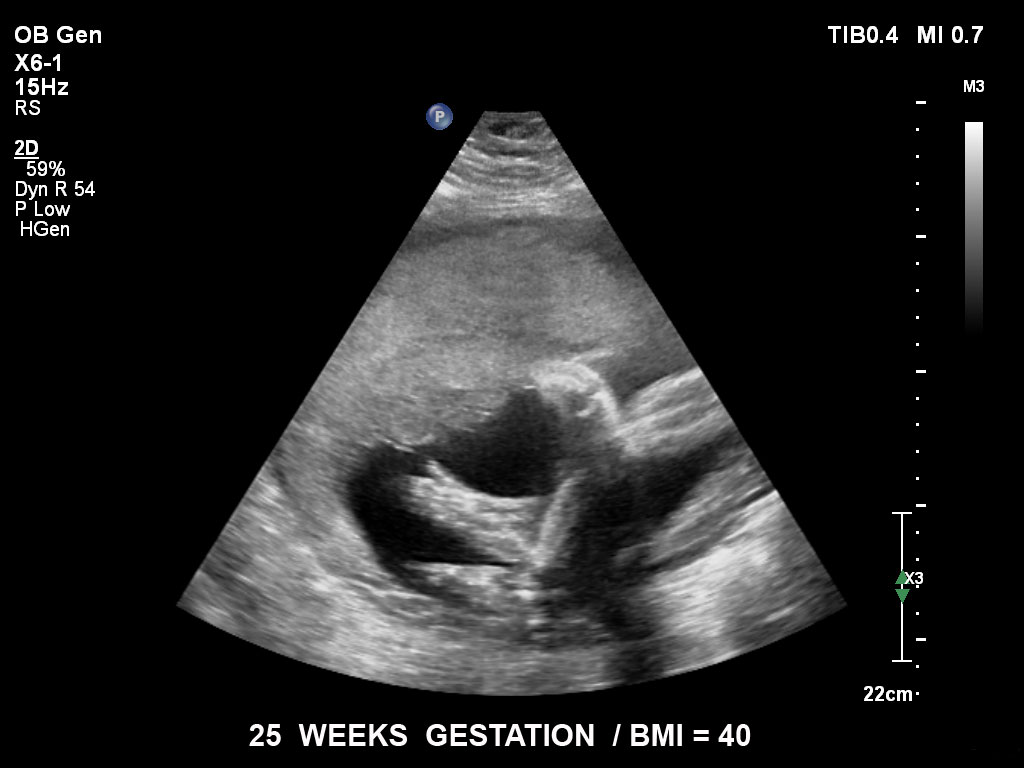

Die EPIQ-Produktreihe mit ausgereiften Schallköpfen erfüllt die Anforderungen auch Ihrer anspruchsvollsten gynäkologischen Untersuchungen und während der gesamten Schwangerschaft.

• C5-1 PureWave-Breitband-Convex-Schallkopf für hohe Eindringtiefen in der Gynäkologie und der Geburtshilfe, für Patientinnen mit Schwangerschaftsdiabetes oder vorzeitigem Blasensprung

• X6-1 PureWave-xMATRIX Schallkopf für diagnostische Anforderungen, die über die 2D-Bildgebung hinausgehen, setzt mit PureWave neue Massstäbe u.a. bei der Live-Volumenbildgebung und Live-Bildgebung in zwei Ebenen gleichzeitig